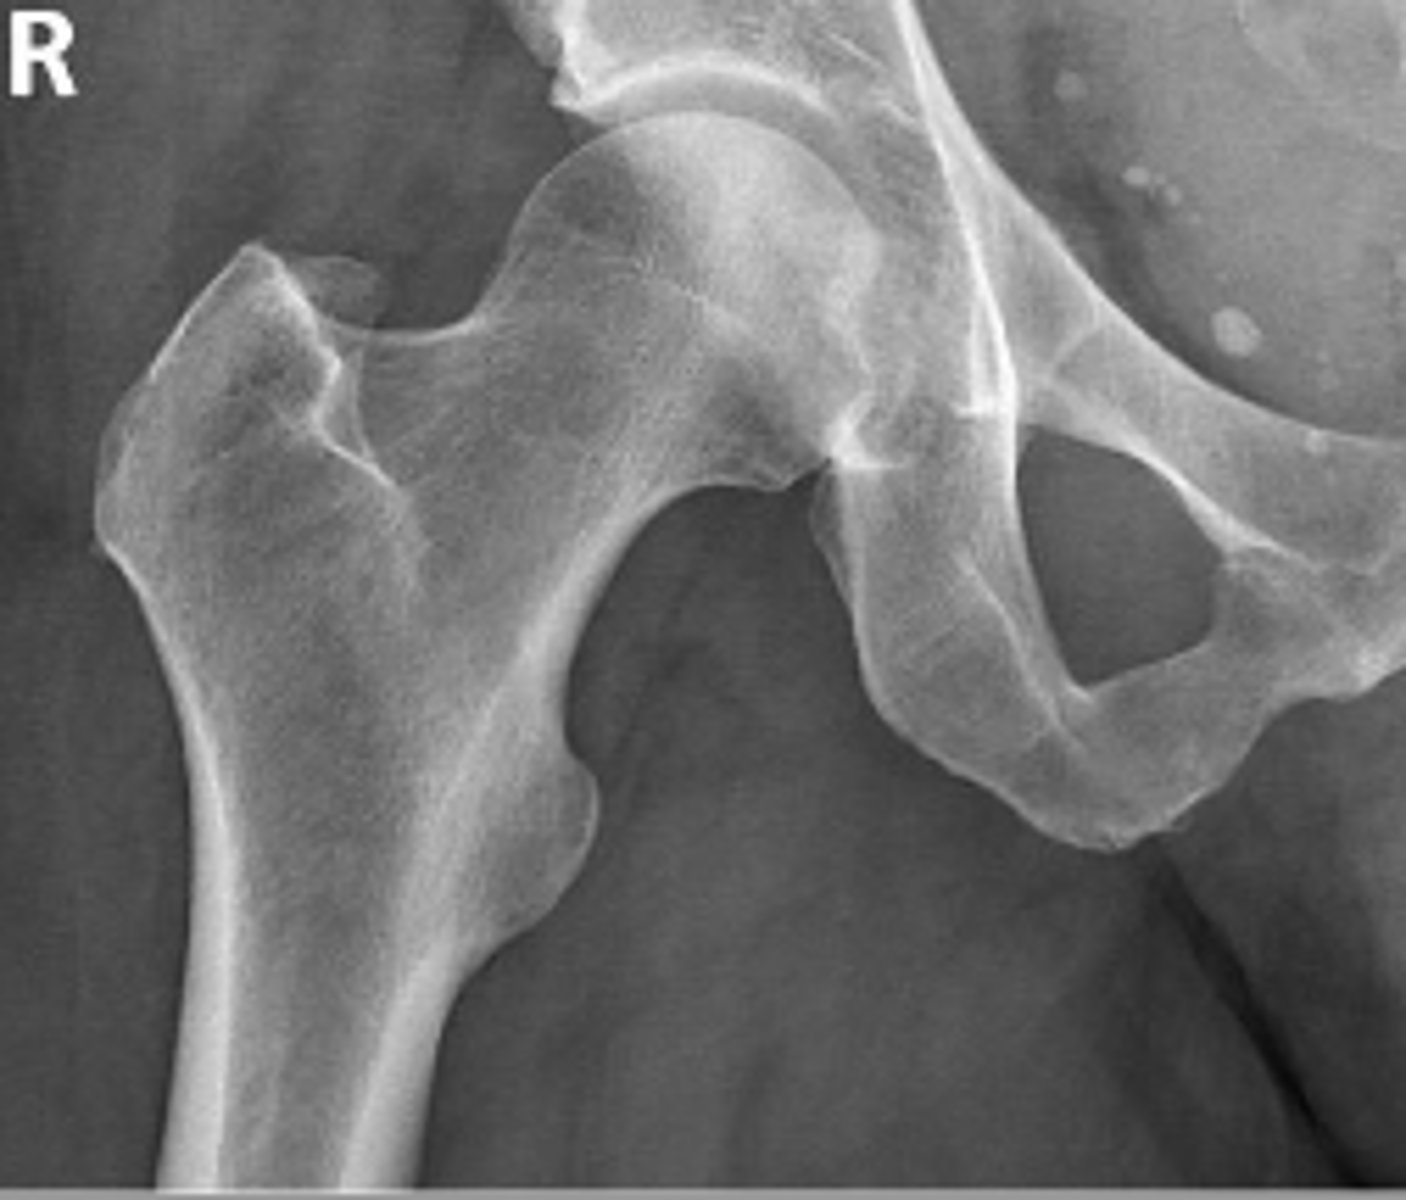

AP right hip

What is the radiographic view?

Teardrop distance

What is the name of the assessment?

6-11mm

What is the normal range for this assessment?

The distance between the most medial margin of

the femoral head and the adjacent pelvic

teardrop

What are the osseous landmarks for this assessment?

Yes (normal is 6-11mm)

Is the measurement within normal limits?

Femoroacetabular joint inflammation

Name 1 condition that may result in a measurement of 15mm?

AP pelvis and AP hip views

Name 2 radiographic views for this assessment?

Late stage degenerative joint disease

Protrusio acetabuli

Name 2 conditions that may result in a measurement of 3mm?

Waldenstrom's sign

What is the named sign if this assessment has a value > 2mm difference

between the left and right side?

Hip joint space width

Superior joint space is 3-6mm

Axial joint space is 3-7mm

Medial joint space is 4-13mm

Superior joint space-> The measurement between the most convex superior aspect of the femoral head and the adjacent acetabulum

Axial joint space -> The measurement between the

femoral head and the acetabulum lateral to the

acetabular notch

Medial Joint space -> The measurement between the most medial margin of the femoral head and the adjacent pelvic teardrop

Yes

Are the measurements within normal limits?

Degenerative joint disease

Name 1 condition that may result in a measurement of <3mm for the superior joint space?